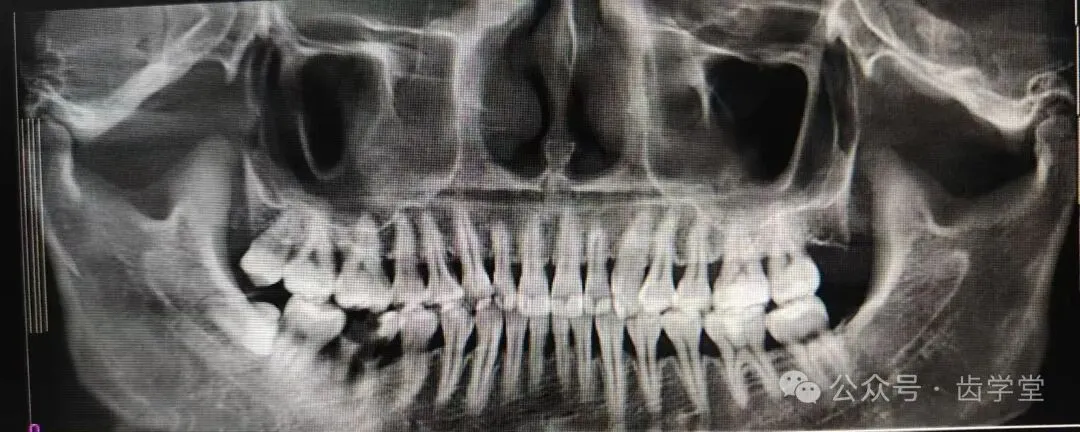

5. 自体牙移植的适应症和禁忌症及其把控;

8. 自体牙移植的术前检查、评估和准备;

23.阻生供牙拔除注意事项;

28.牙槽内移植详解;

29.意向性再植详解;